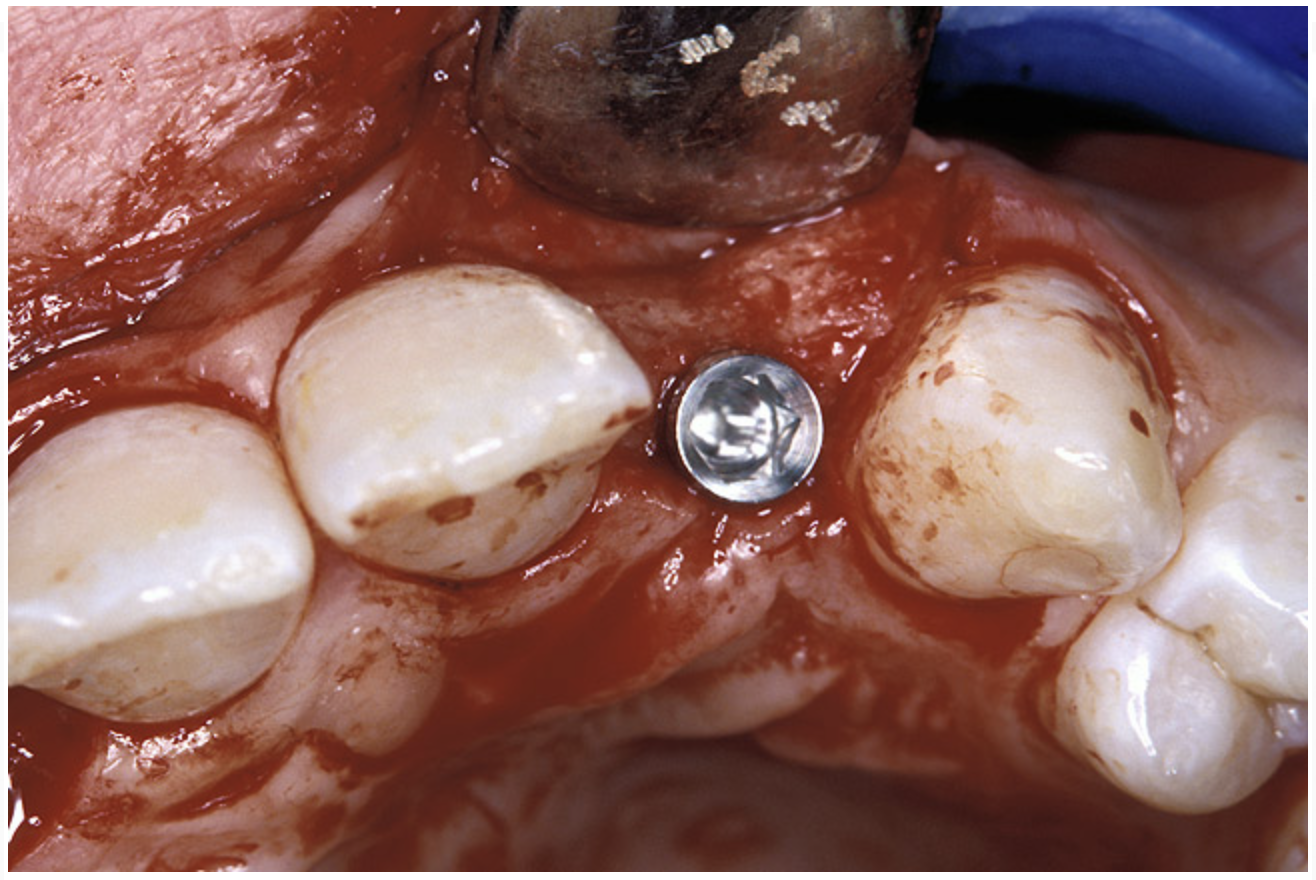

The 3.7-mm diameter Tapered Screw-Vent implant drilling sequence required three drills: pilot, intermediate, and final sizing. Thus, three separate templates were fabricated to accommodate these sizes. The templates were removed easily and replaced with the next sequential size in less time than it takes to change the drill on the surgical handpiece. After the osteotomies had been completed, the implants were delivered to the site (Figure 16A and Figure 16B). For this internal hex connection implant, the author r.commends that the flat of the antirotational hex be positioned to the facial for proper orientation of the restorative components (Figure 17A). Preprepared margins were created from a milled titanium fixture mount transfer post, which was delivered to the implant as support for an immediate transitional restoration. The facial “dot” helped confirm the orientation of the abutment to the facially positioned flat side of the internal hex connection (Figure 17B). Before cementation of the transitional acrylic restorations, a closed-tray, fixture-level impression was made, and a soft-tissue model fabricated.

Figure 16a  After (A) the osteotomies were completed, (B) the implants were placed.

Figure 16a

Figure 16b  After (A) the osteotomies were completed, (B) the implants were placed.

Figure 16b